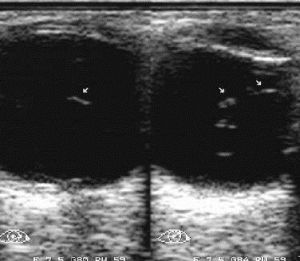

- УЗИ выявляет изменения и помутнения сред глаза

Узи при хориоретините